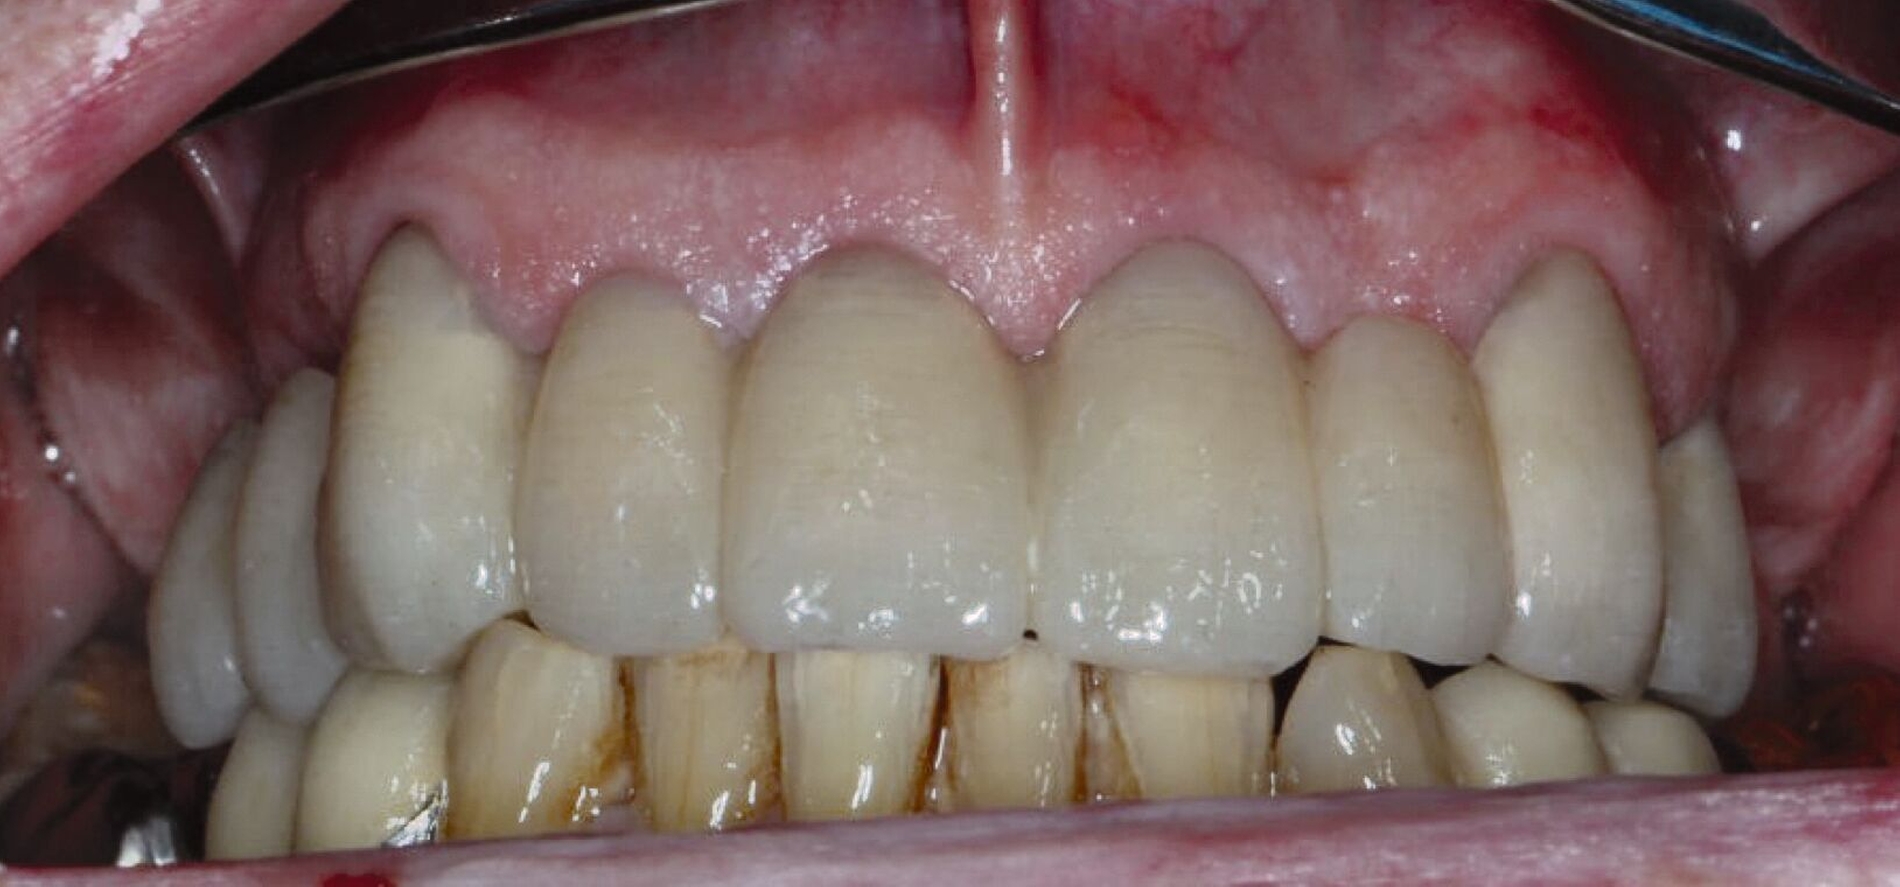

Der Patient stand unter der Dauermedikation von Metformin 500 mg, Ramipril 5 mg, Torasemid 10 mg, Metohexal 47,5 mg, Simvastatin 20 mg, Tamsulosin 0,4 mg und 3 mg Marcumar (INR 2,5–2,8) bei Zustand nach einer Bypass-Operation im Jahr 2019. Klinisch zeigten sich im Oberkiefer insuffiziente, verblockte und verblendete NEM-Kronen mit beidseitigen Gold-Extensionen distal, die über Geschiebe mit dem anterioren Anteil verschraubt waren (Abbildungen 1 und 2). Der Patient berichtete, dass die vorhandenen Kronen und Brücken 1984 eingesetzt worden seien.

Übergangsweise wurden die verbliebenen Stümpfe mit einem festsitzenden Langzeitprovisorium aus einem Hochleistungspolymer der PET-Gruppe versorgt (Abbildung 4), um Stabilität über einen längeren Zeitraum gewährleisten zu können. Nach der Extraktion des Zahnes 14 und der Abheilung der Extraktionswunde wurde der Patient über die Optionen des definitiven Zahnersatzes aufgeklärt: